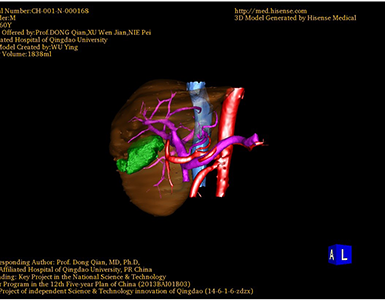

CT结果输入海信CAS系统后行3D重建及手术规划后,于2016-8-03全麻下行“脾切除术”手术治疗:

术前三维重建及手术方案设计:

将0.625mm双源薄层CT资料的静脉期和动脉期Dicom格式文件导入海信CAS系统。

通过调节窗宽窗位调整CT序号,对肿瘤,肝实质,胆囊,下腔静脉,肿瘤,肝动脉、门静脉及肝静脉等进行三维重建;系统自动计算肿瘤体积和肝脏体积。

术前手术方案的规划。

术前三维重建:

重建图片